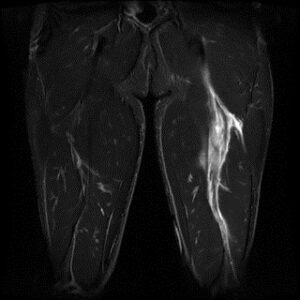

• MRI検査:より深部の損傷や、完全断裂の疑いがある場合の詳細な評価、重症度評価を行います。

*右:筋膜(黒)の連続性がない     左:ハムストリング筋内に沿って広範に損傷、出血している